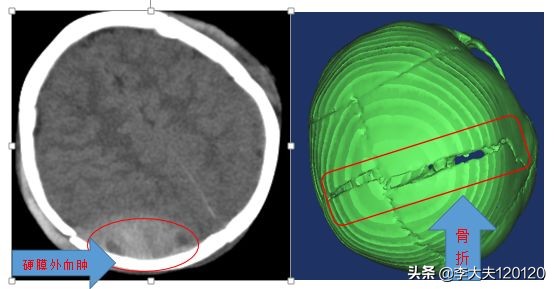

急诊查头颅CT:双侧额顶部硬膜外血肿、顶骨骨折、顶枕部皮下血肿。

见到患儿时,患儿处于昏睡状态,急诊头颅CT显示“硬膜外血肿、顶骨骨折”, 情况非常危急。